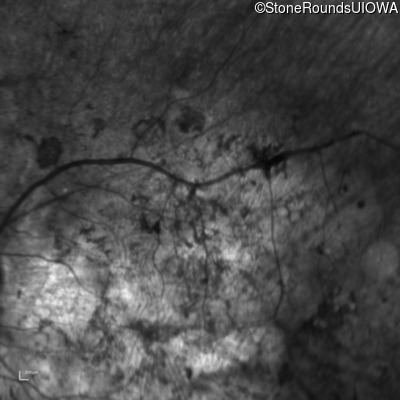

Infrared Fundus Photograph - Right - Hand Motion

Exemplar